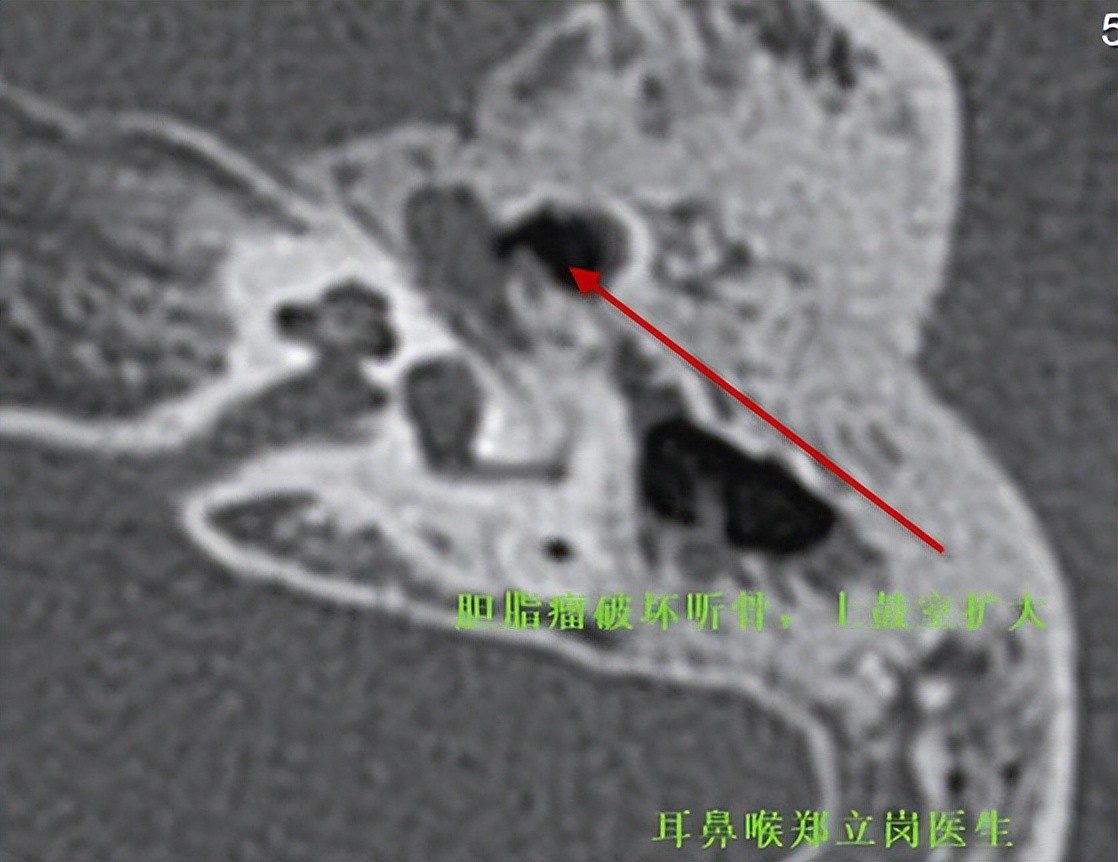

胆脂瘤中耳炎,小切口微创手术彻底解决

对于一般范围比较小的胆脂瘤中耳炎或者中等范围的胆脂瘤中耳炎患者来说,不做任何切口的耳内镜胆脂瘤中耳炎手术是比较好的选择。但是对于部分严重的胆脂瘤中耳炎,范围比较大,做耳内镜胆脂瘤微创手术就比较难,这个时候做耳后大切口的手术必要性也是没有的。耳前小切口微创手术对于大范围严重的胆脂瘤中耳炎来说是非常好的选择。最近,耳鼻喉郑立岗医生就为一位年轻的胆脂瘤中耳炎患者做了小切口胆脂瘤微创手术。

患者黄,男,19岁,广东云浮人。患者10余年前无明显诱因开始出现左耳流淡黄色脓,量少,无特殊臭味,无伴有豆渣样物,无带血液,伴左耳听力轻度下降、耳鸣,曾多次到外院门诊,予消炎药物治疗后症状有所缓解,今特来我院门诊检查,为进一步诊治,门诊拟胆脂瘤中耳炎收住我科,入院时患者病情一般。

患者入院后评估胆脂瘤范围比较广泛,患者又比较胖,做耳内镜胆脂瘤微创手术不是非常适合,这次就做了全麻小切口胆脂瘤中耳炎微创手术。在耳前做了2cm左右的小切口,逐层地暴露乳突骨皮质,电钻打开鼓窦及上鼓室,可见鼓窦及上鼓室中较多的胆脂瘤组织。术中予以彻底的清除胆脂瘤组织后,用部分人工听骨重建了听骨链。整个手术用时约3个小时,术后查房患者无明显的不适,无手术相关的并发症。